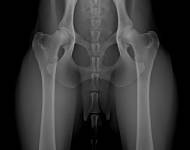

MVDr. Meloun: Lumbosakrální přechodový obratel